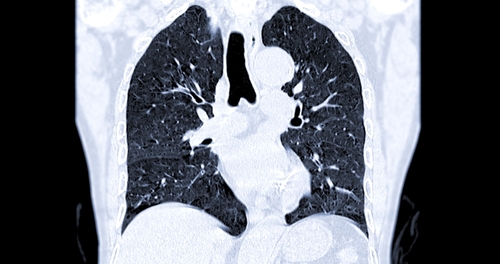

Dilansir dari Healthline, emboli paru adalah gumpalan darah yang terjadi di paru-paru. Ini dapat merusak bagian paru-paru karena aliran darah yang terbatas, menurunkan kadar oksigen dalam darah, dan memengaruhi organ lain juga.

Penggumpalan darah yang besar atau banyak, bahkan bisa mengakibatkan kematian. Perawatan darurat dengan segera sangat diperlukan untuk menurunkan potensi kerusakan paru-paru permanen.